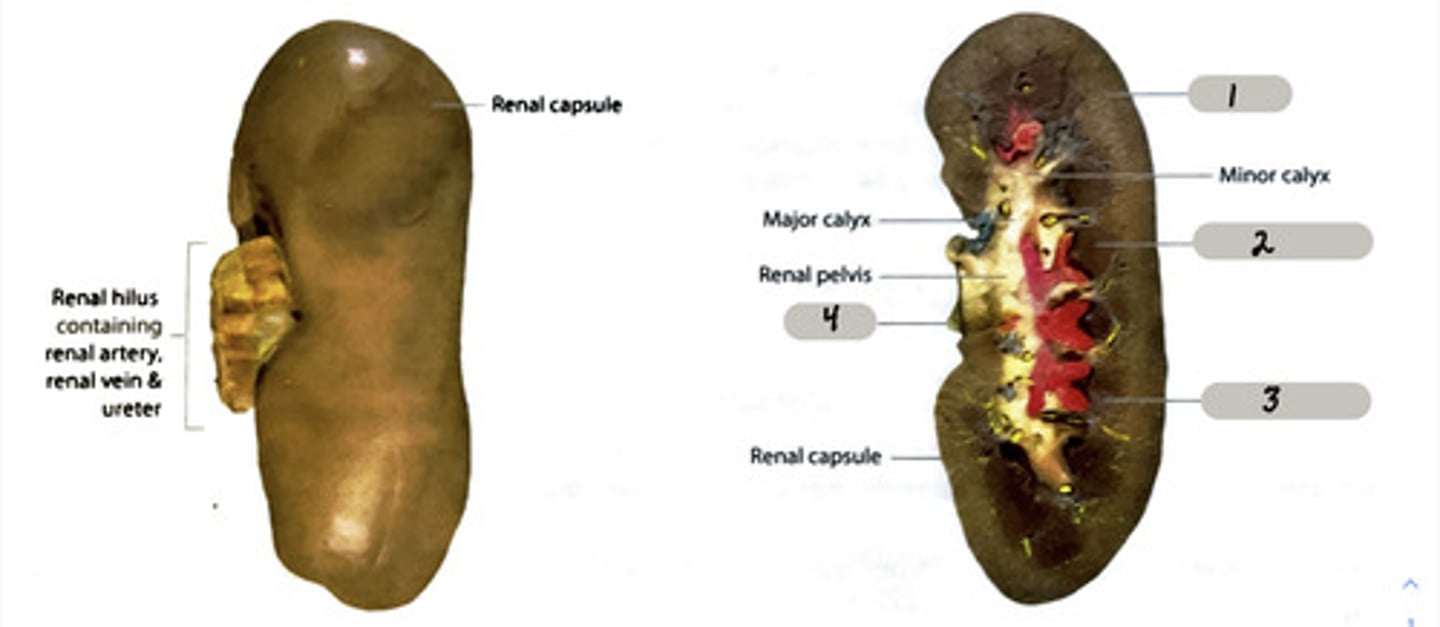

Urinary-kidneys, ureters, urinary bladder, uretha

form urine in order to maintain water balance salt balance, pH, and nitrogenous waste levels in the blood

renal pyramid

2

renal column

3

cortex

outer layer of the kidney

ureter

A duct leading from the kidney to the urinary bladder.

nephron

the functional unit of the kidney

Adrenal gland